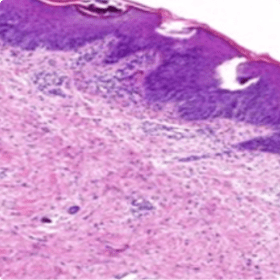

COMMON SIGNS AND SYMPTOMS OF GPP INCLUDE PUSTULES, ERYTHEMA, AND PERSISTENT LESIONS2–4

GPP skin lesions

Image used with permission from Dr. Siew Eng Choon.